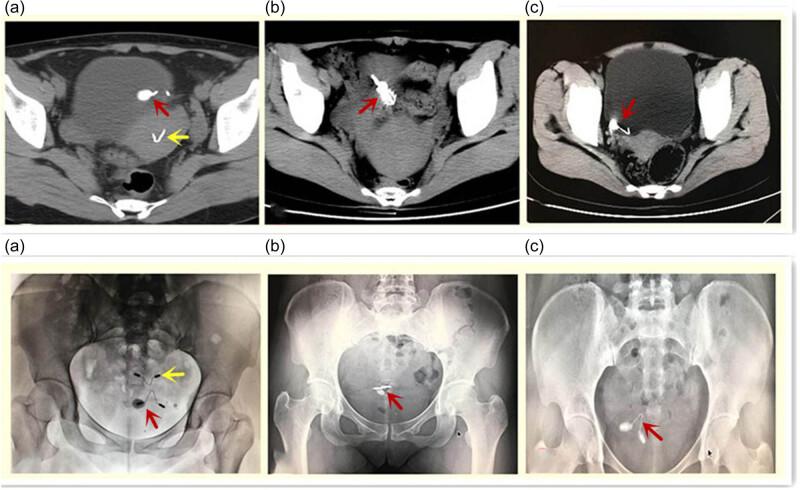

Bladder-embedded ectopic intrauterine device with calculus.

The present study aimed to analyze the data of embedded intrauterine device (IUD) in the bladder wall with the additional presence of calculus. This case series study included 11 female patients with partially or completely embedded IUD in the bladder wall. Their median age was 34 (range, 32-39) years. The median duration of IUD placement was 36 (range, 24-60) months. The median duration of symptoms was 9 (range, 3-12) months. Six patients underwent laparoscopy: the operation duration was 129 (range, 114-162) min, blood loss was 15 (range, 10-25) mL, the hospital stay was 4 (range, 4-4.5) days, the visual analog scale (VAS) for pain at 6 h after surgery was 3 (range, 2-6), and the time to removal of the urethral catheter was 7 (range, 7-8) days. Five patients underwent open surgery: the operation duration was 126 (range, 96-192) min, blood loss was 30 (range, 20-50) mL, the hospital stay was 7 (range, 7-15) days, the VAS was 6 (range, 4-9) at 6 h after surgery, and the time to removal of the urethral catheter was 9 (range, 8-17) days. The IUD and bladder stones were successfully removed in all 11 (100%) patients.